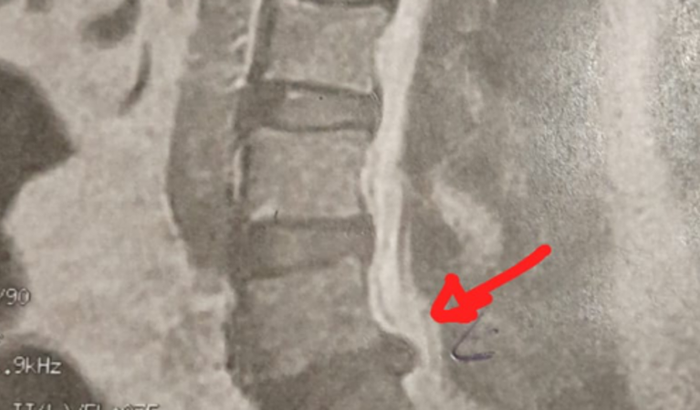

Eu sou Andréa, criei essa vaquinha para conseguir arrecadar 15 mil reais para minha cirugia de extrema urgência. Onde eu fico impossibilitada de andar as vezes é até de fazer minhas necessidades do dia a dia e até fisiológicas! Estou andando com ajuda de andandor, apoiador e entre outras coisas, as vezes não consigo ficar em pé, pois perco as forças nas pernas e até mesmo caio no chão, estou desempregada e impossíbilitada de trabalhar fora, queria muito que vocês conseguissem me ajudar a fazer essa cirurgia para de novo ter a minha vida de volta e conseguir fazer minhas coisinhas novamente, agradeço desde já!